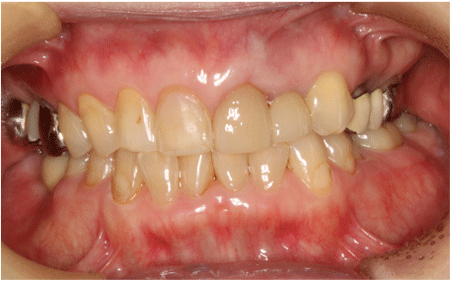

インプラントセラミック

2026.04.0550代男性 欠損していた下左右奥歯にインプラントを埋入してしっかりと噛めるように治療した症例